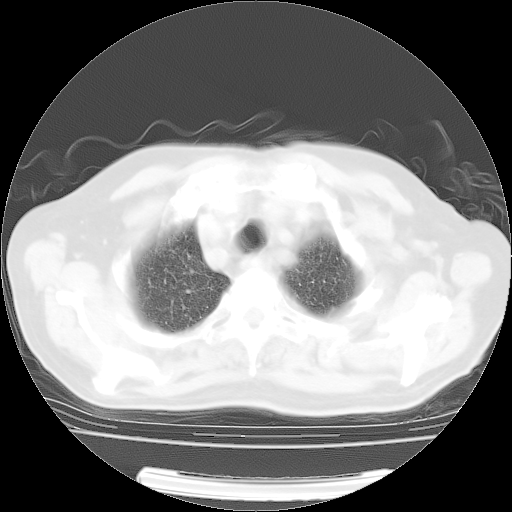

肺部CT平扫未见异常。